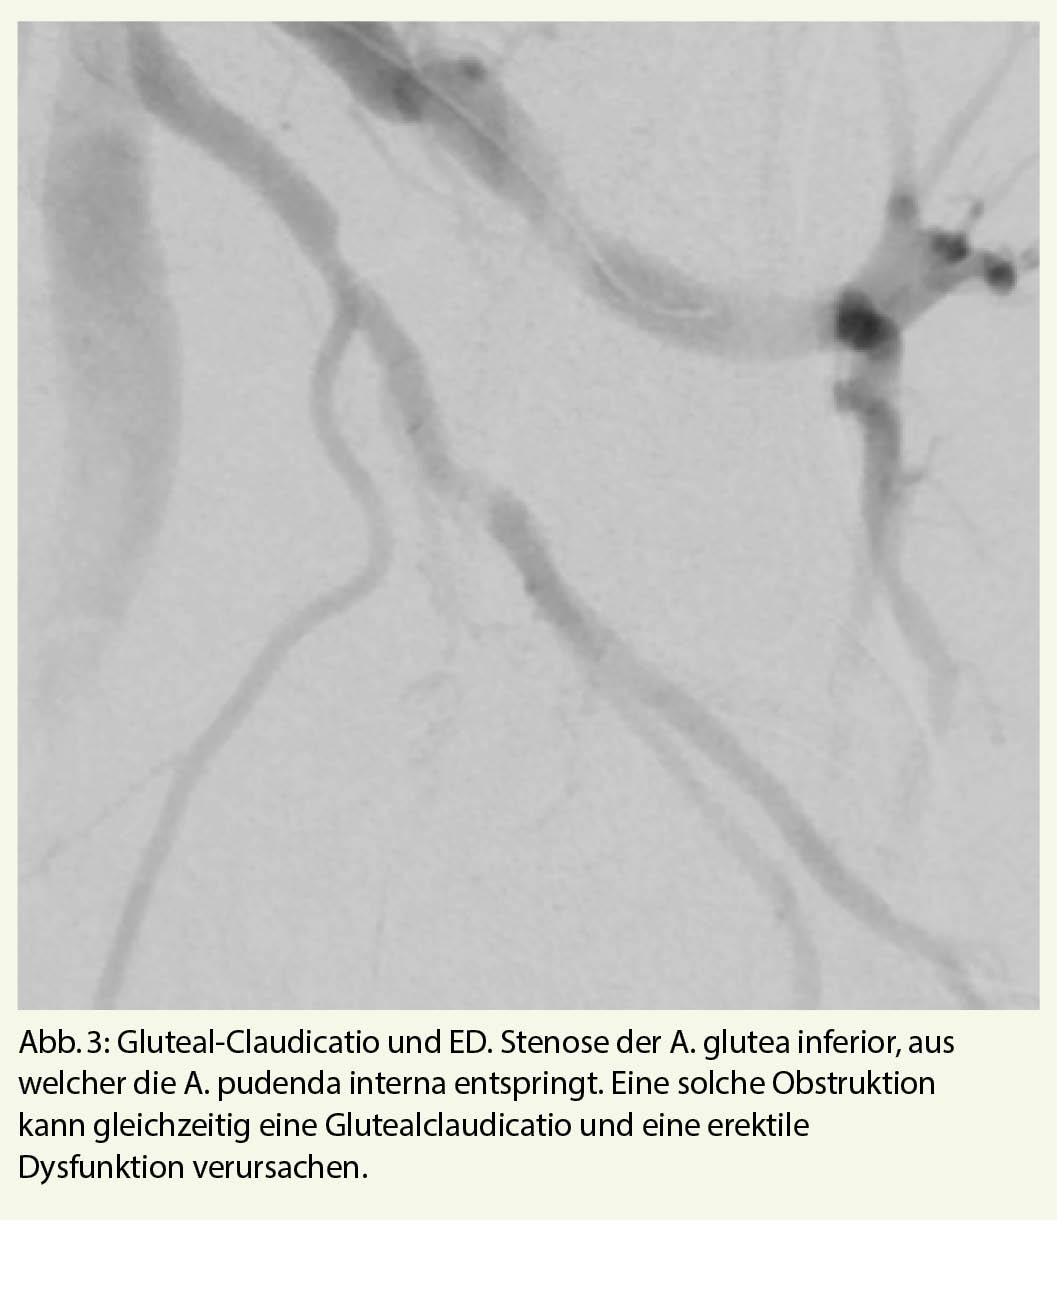

Zwischenzeitlich hat die Miniaturisierung des Kathetermaterials die endovaskuläre Therapie von Arterien kleinen Kalibers ermöglicht (12, 13). In Analogie zu den Entwicklungen der Kathetertherapie wagen sich heute erfahrene Interventionalisten nun immer tiefer in die Penis-versorgenden Arterien vor. Bei Obstruktionen der A. iliaca interna oder der A. glutea inferior kann neben einer arteriell bedingten ED auch eine Glutealclaudicatio vorliegen. Mit einer Katheter-Revaskularisation kann man hier häufig zwei Fliegen mit einer Klappe schlagen (Abb. 3).